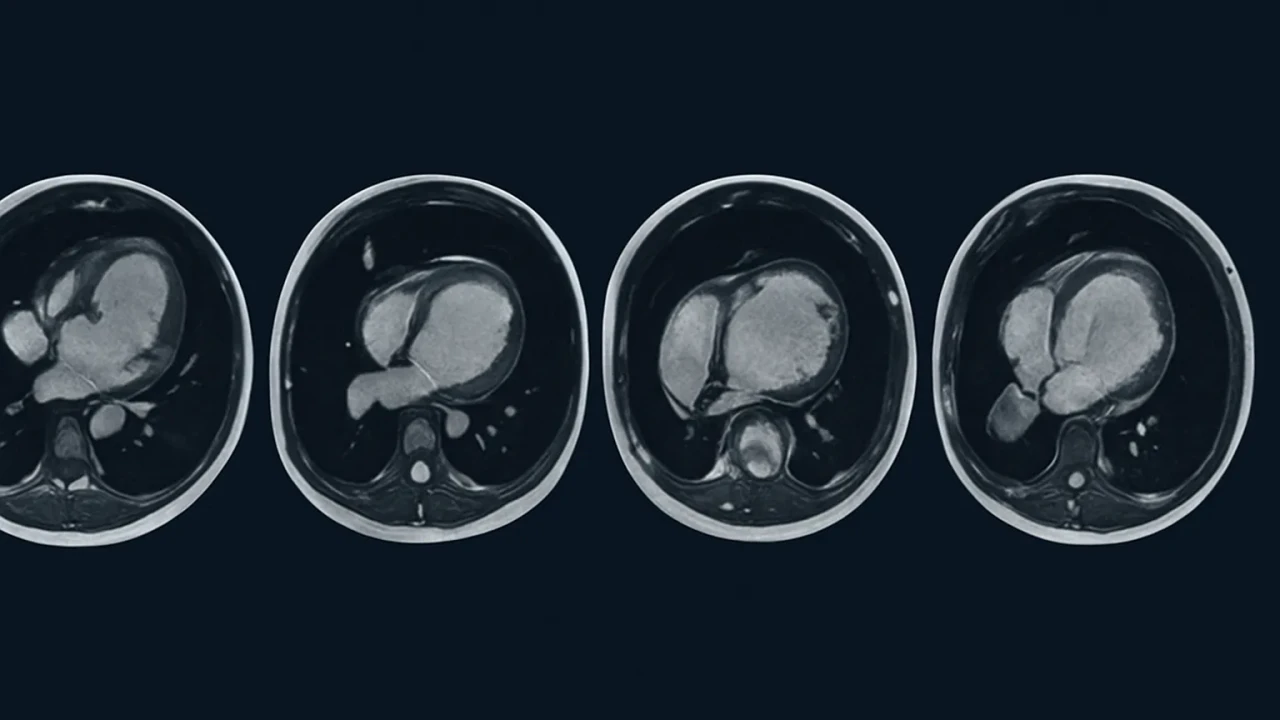

Sessiz tehlikeye karşı MRI umudu

Yapay zekâ destekli kalp MRI’ları, ölümcül kardiyomiyopati gibi hastalıkların teşhisinde devrim yaratıyor.

Cambridge Üniversitesi liderliğinde gerçekleştirilen araştırmada, yüz binlerce bireyin MRI kalp taramaları incelendi. Yapay zekâ destekli analiz yöntemleri kullanılarak kalp kaslarının kalınlığı ve yapısal bütünlüğü değerlendirildi. Elde edilen veriler, sessiz ilerleyen kardiyomiyopati gibi ciddi kalp hastalıklarının geleneksel yöntemlerle gözden kaçabileceğini, ancak MRI ile tespit edilebildiğini gösterdi.

Kardiyomiyopati Gibi Hastalıklar Artık Saklanamayacak

Kalp kasının zayıflaması ya da yapısal bozulmaya uğraması sonucu ortaya çıkan kardiyomiyopati, çoğu zaman sessiz seyreder. Fakat bu hastalık, ani kalp durmalarına kadar ilerleyebilir. MRI taramaları sayesinde kalp kaslarındaki küçük değişimler bile fark edilerek erken müdahale şansı doğuyor. Araştırma ayrıca kalp kasının kalınlaşma seviyesinin, kalp krizi ve ani ölüm riskleriyle doğrudan ilişkili olduğunu da ortaya koydu.